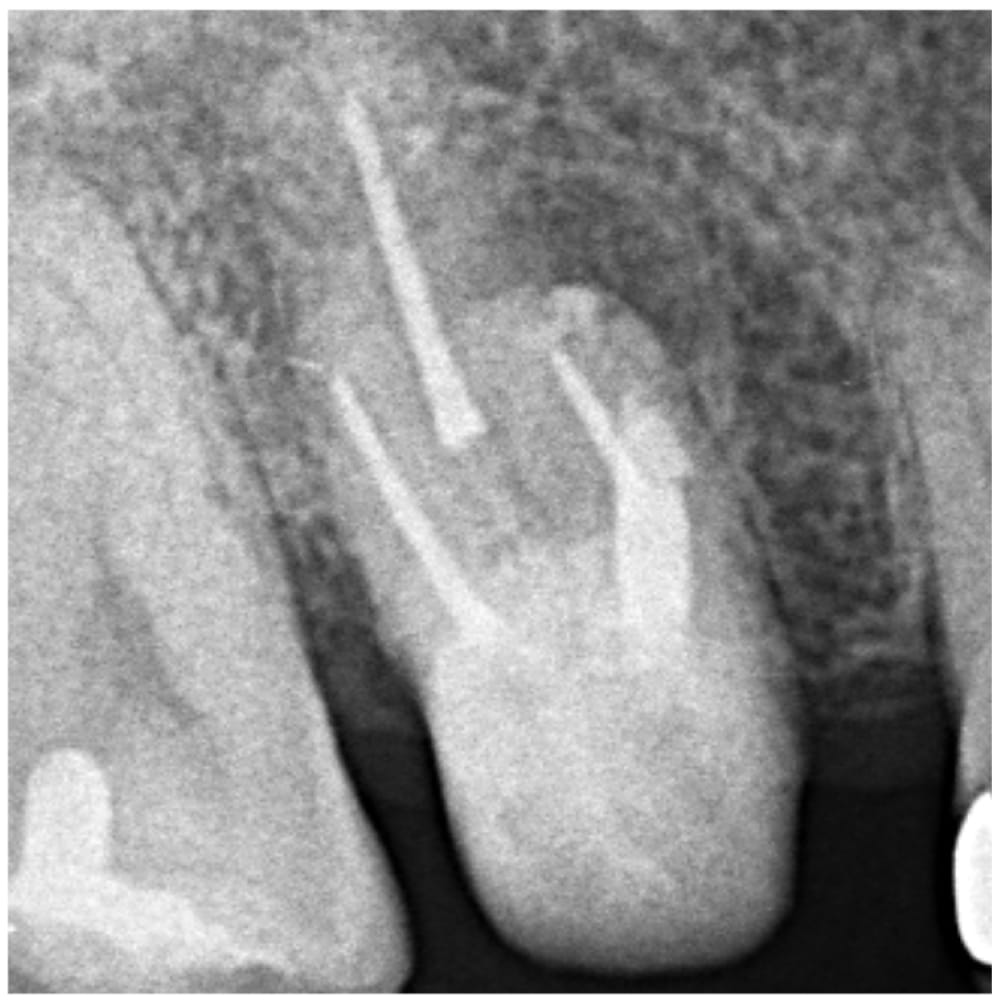

右上の6番(第一大臼歯)に、根の先の黒い影(根尖性歯周炎)と、その根管内に破折ファイルと思われる不透過像が認められる状態でした。器具が残っているから治らないというわけではありませんが、器具がある部分は根管内の清掃・感染源の除去が十分に行えないため、可能であれば除去する方針で治療を進めることになりました。根の湾曲はそこまでなく、破折位置も浅いことから、おそらく除去は比較的容易と判断しました。